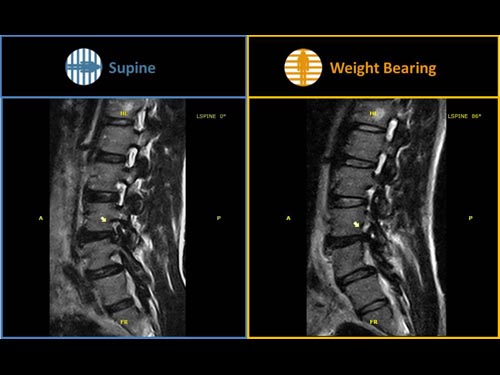

Nová končetinová magnetická rezonance G-scan Brio od společnosti Esaote je tomografický systém MRI, který umožňuje studium všech kloubů i páteře, ať už v klinostatické (vleže) nebo ortostatické (vážící) poloze, protože magnet i pacient se mohou otáčet od 0 do 90 stupňů. Díky inovativnímu designu G-scan mohou být pacienti Brio skenováni v poloze nesoucí váhu, aby se usnadnila diagnostika MSK u těch patologií, které se mohou měnit v důsledku držení těla a polohy, jako jsou bolesti dolní části zad.

• Další diagnostické schopnosti: jelikož gravitační síla generuje bio-mechanické změny v anatomii, MR zobrazení v přirozené poloze ve stoje vám umožňuje dosáhnout důležitých dalších informací ve srovnání s tradičními MRI